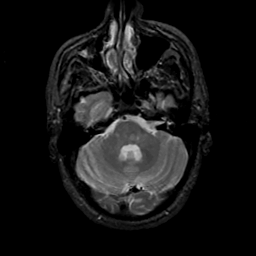

MR Study #19, August 25, 1991 -- Slice #12